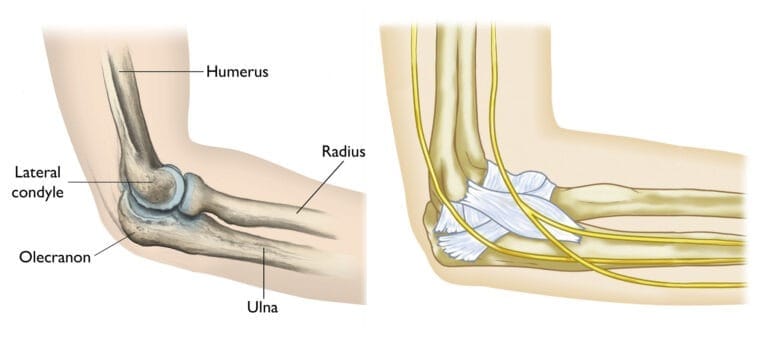

Anatomy

The elbow is a joint made up of three bones:

- The humerus (upper arm bone)

- The radius (forearm bone on the thumb side)

- The ulna (forearm bone on the pinky side)

The elbow joint bends and straightens like a hinge. It is also important for rotation of the forearm: that is, the ability to turn your palm up (like accepting change from a cashier) or palm down (like typing or playing the piano).The elbow consists of portions of all three bones:

- The distal humerus is the lower end of the humerus. It forms the upper part of the elbow and is the spool around which the forearm bends and straightens.

- The radial head is the knobby end of the radius where it meets the elbow. It glides up and down the front of the distal humerus when you bend your arm and rotates around the ulna when you turn your wrist up or down.

- The olecranon is the part of the ulna that cups the lower end of the humerus, creating a hinge for elbow movement. The bony point of the olecranon can easily be felt beneath the skin because it is covered by just a thin layer of tissue.

The elbow is held together by its bony architecture, as well as ligaments, tendons, and muscles. Three major nerves cross the elbow joint.